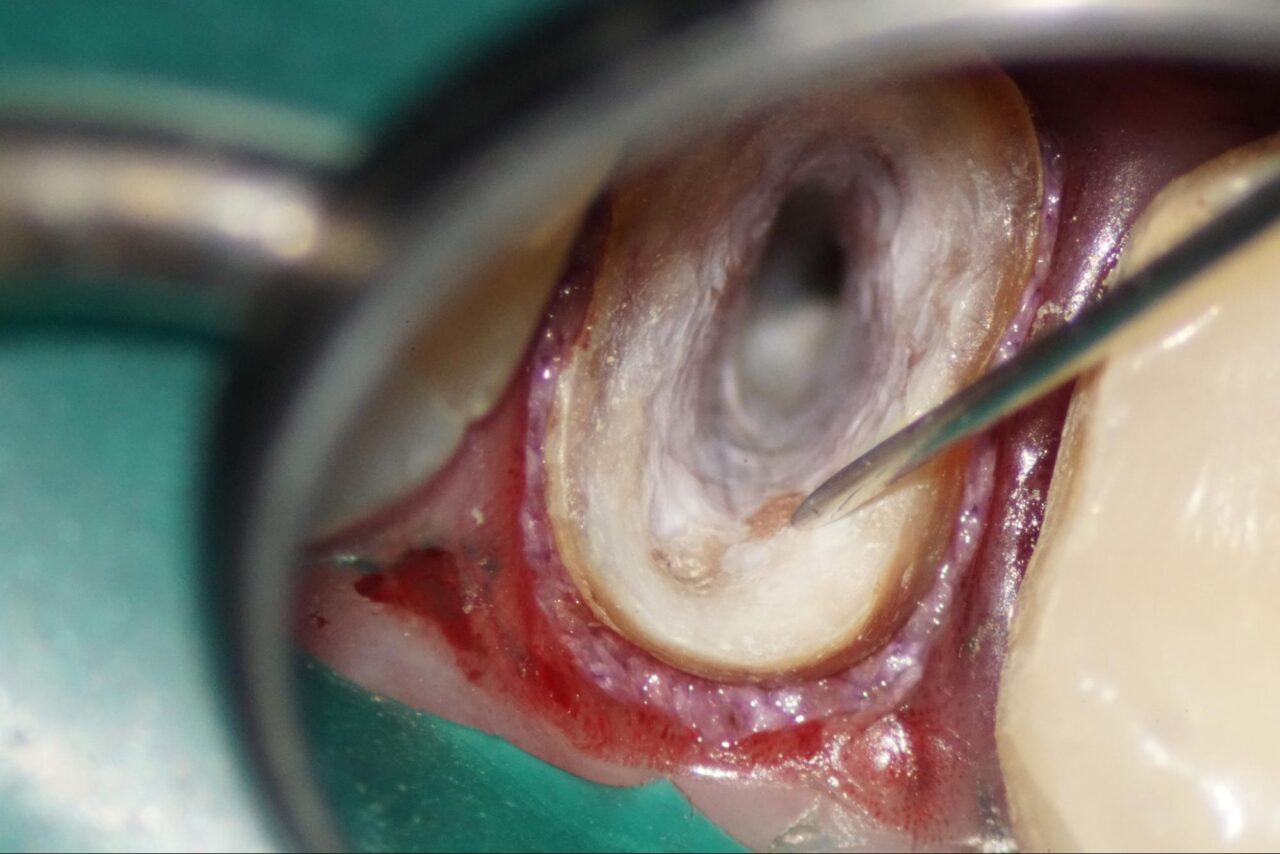

ラバーダムシートが被って触れていない部分があるので、一部ラバーダムシートを破って患歯を露出させて次のステップための準備をいたします。

頬側根はヒビが白くスジ状になっている事が確認できます。

根尖部分位は以前の先生が治療したものがまだ残っていることが確認できます。

根の先、根尖部分から感染している根管充填材が取れました。

頬側根のクラックラインは、感染してる様ではないので、その後せ着の操作に移ります。